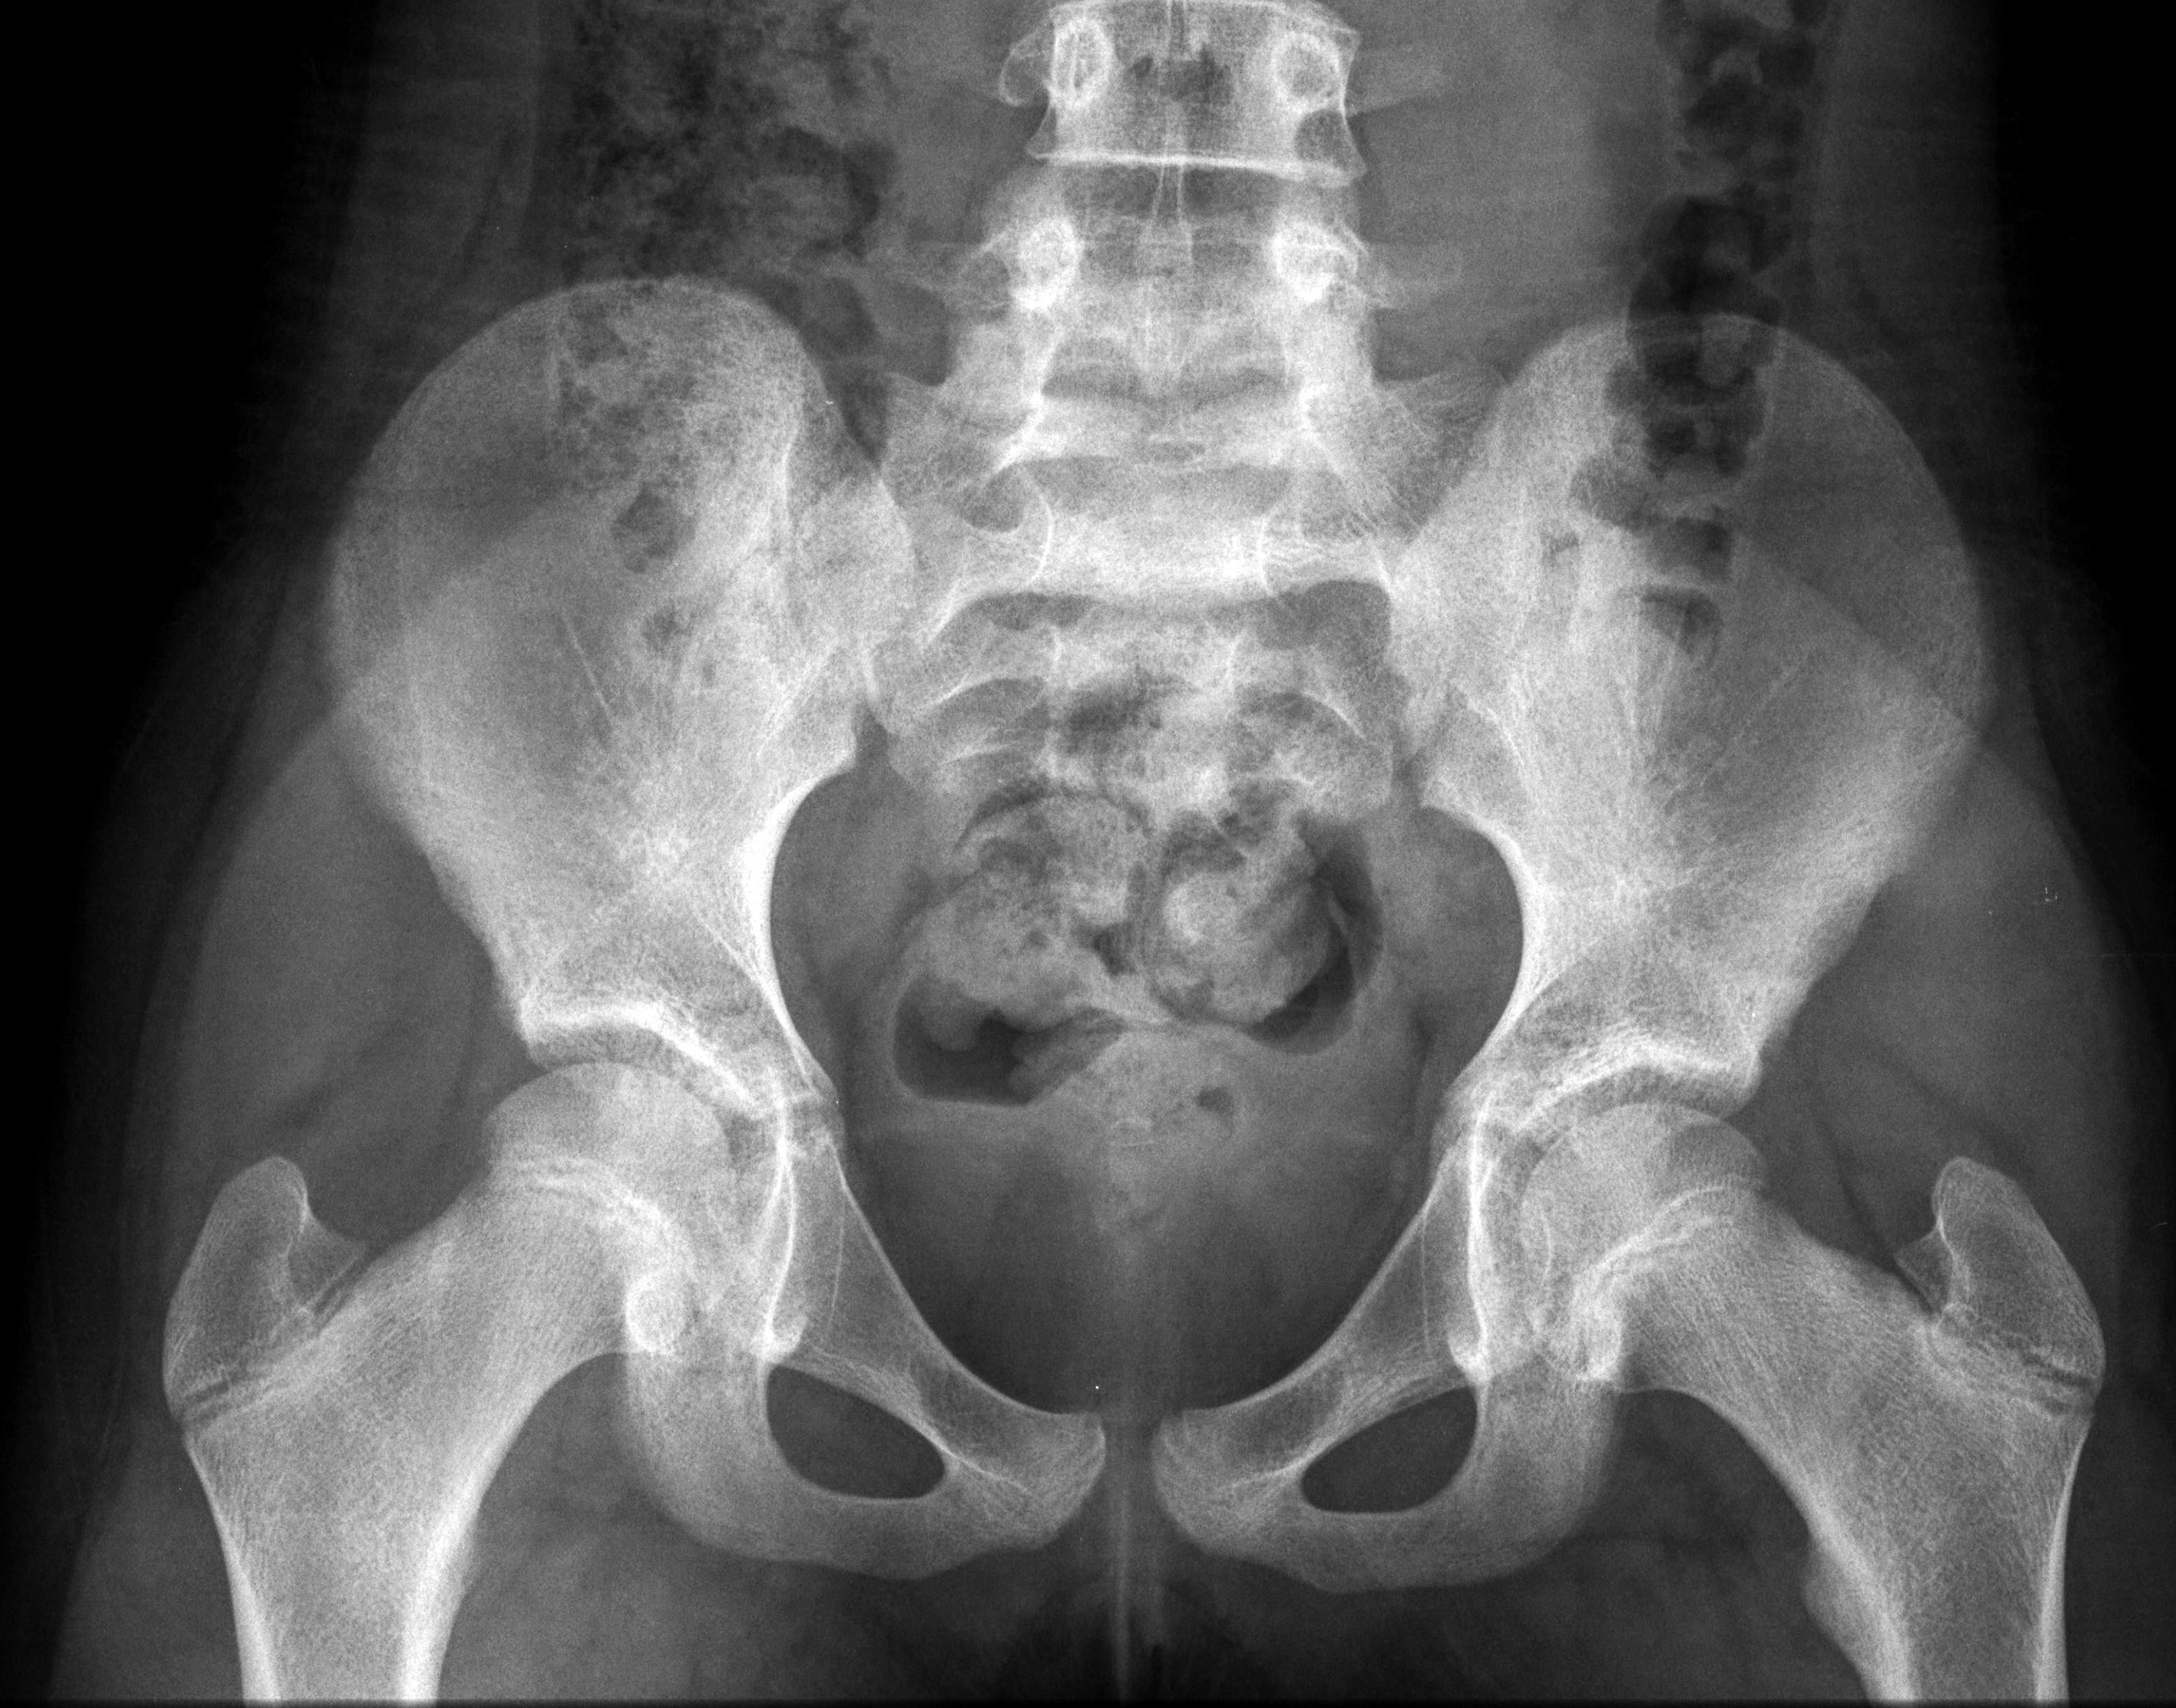

El principal problema es que la pelvis de las niñas es demasiado estrecha como para que pueda pasar incluso un feto pequeño, señaló Ashok Dyalchand, un médico que ha trabajado con adolescentes embarazadas en comunidades de bajos ingresos en la India durante más de 40 años.

“La labor de parto que experimentan es prolongada y obstruida, el feto aplasta la vejiga y la uretra” y a veces provoca la enfermedad pélvica inflamatoria y la ruptura de los tejidos que hay entre la vagina y la vejiga y el recto, señaló Dyalchand, quien dirige el Instituto de Gestión Sanitaria Pachod, que es una organización de salud pública que atiende a las comunidades marginadas en la zona central de la India.

En los casos que él ha visto, el embarazo temprano frena el desarrollo físico de las madres muy jóvenes y, con frecuencia, también el desarrollo mental debido a que muchas niñas dejan la escuela y se pierden de la interacción social normal con sus compañeros, comentó Syed. Pero, pese a que una madre anémica tiene problemas para llevar el embarazo, el feto se apropia de los nutrientes y sigue creciendo hasta que supera por mucho lo que puede dejar pasar la pelvis de una madre muy joven.

En casi todos estos casos, la niña desarrolla una fístula vesicovaginal, que es un agujero entre la pared de la vejiga y la vagina. En una cuarta parte de los casos, el trabajo de parto prolongado también origina una fístula del recto, por lo que la chica deja salir orina y excremento de manera constante.